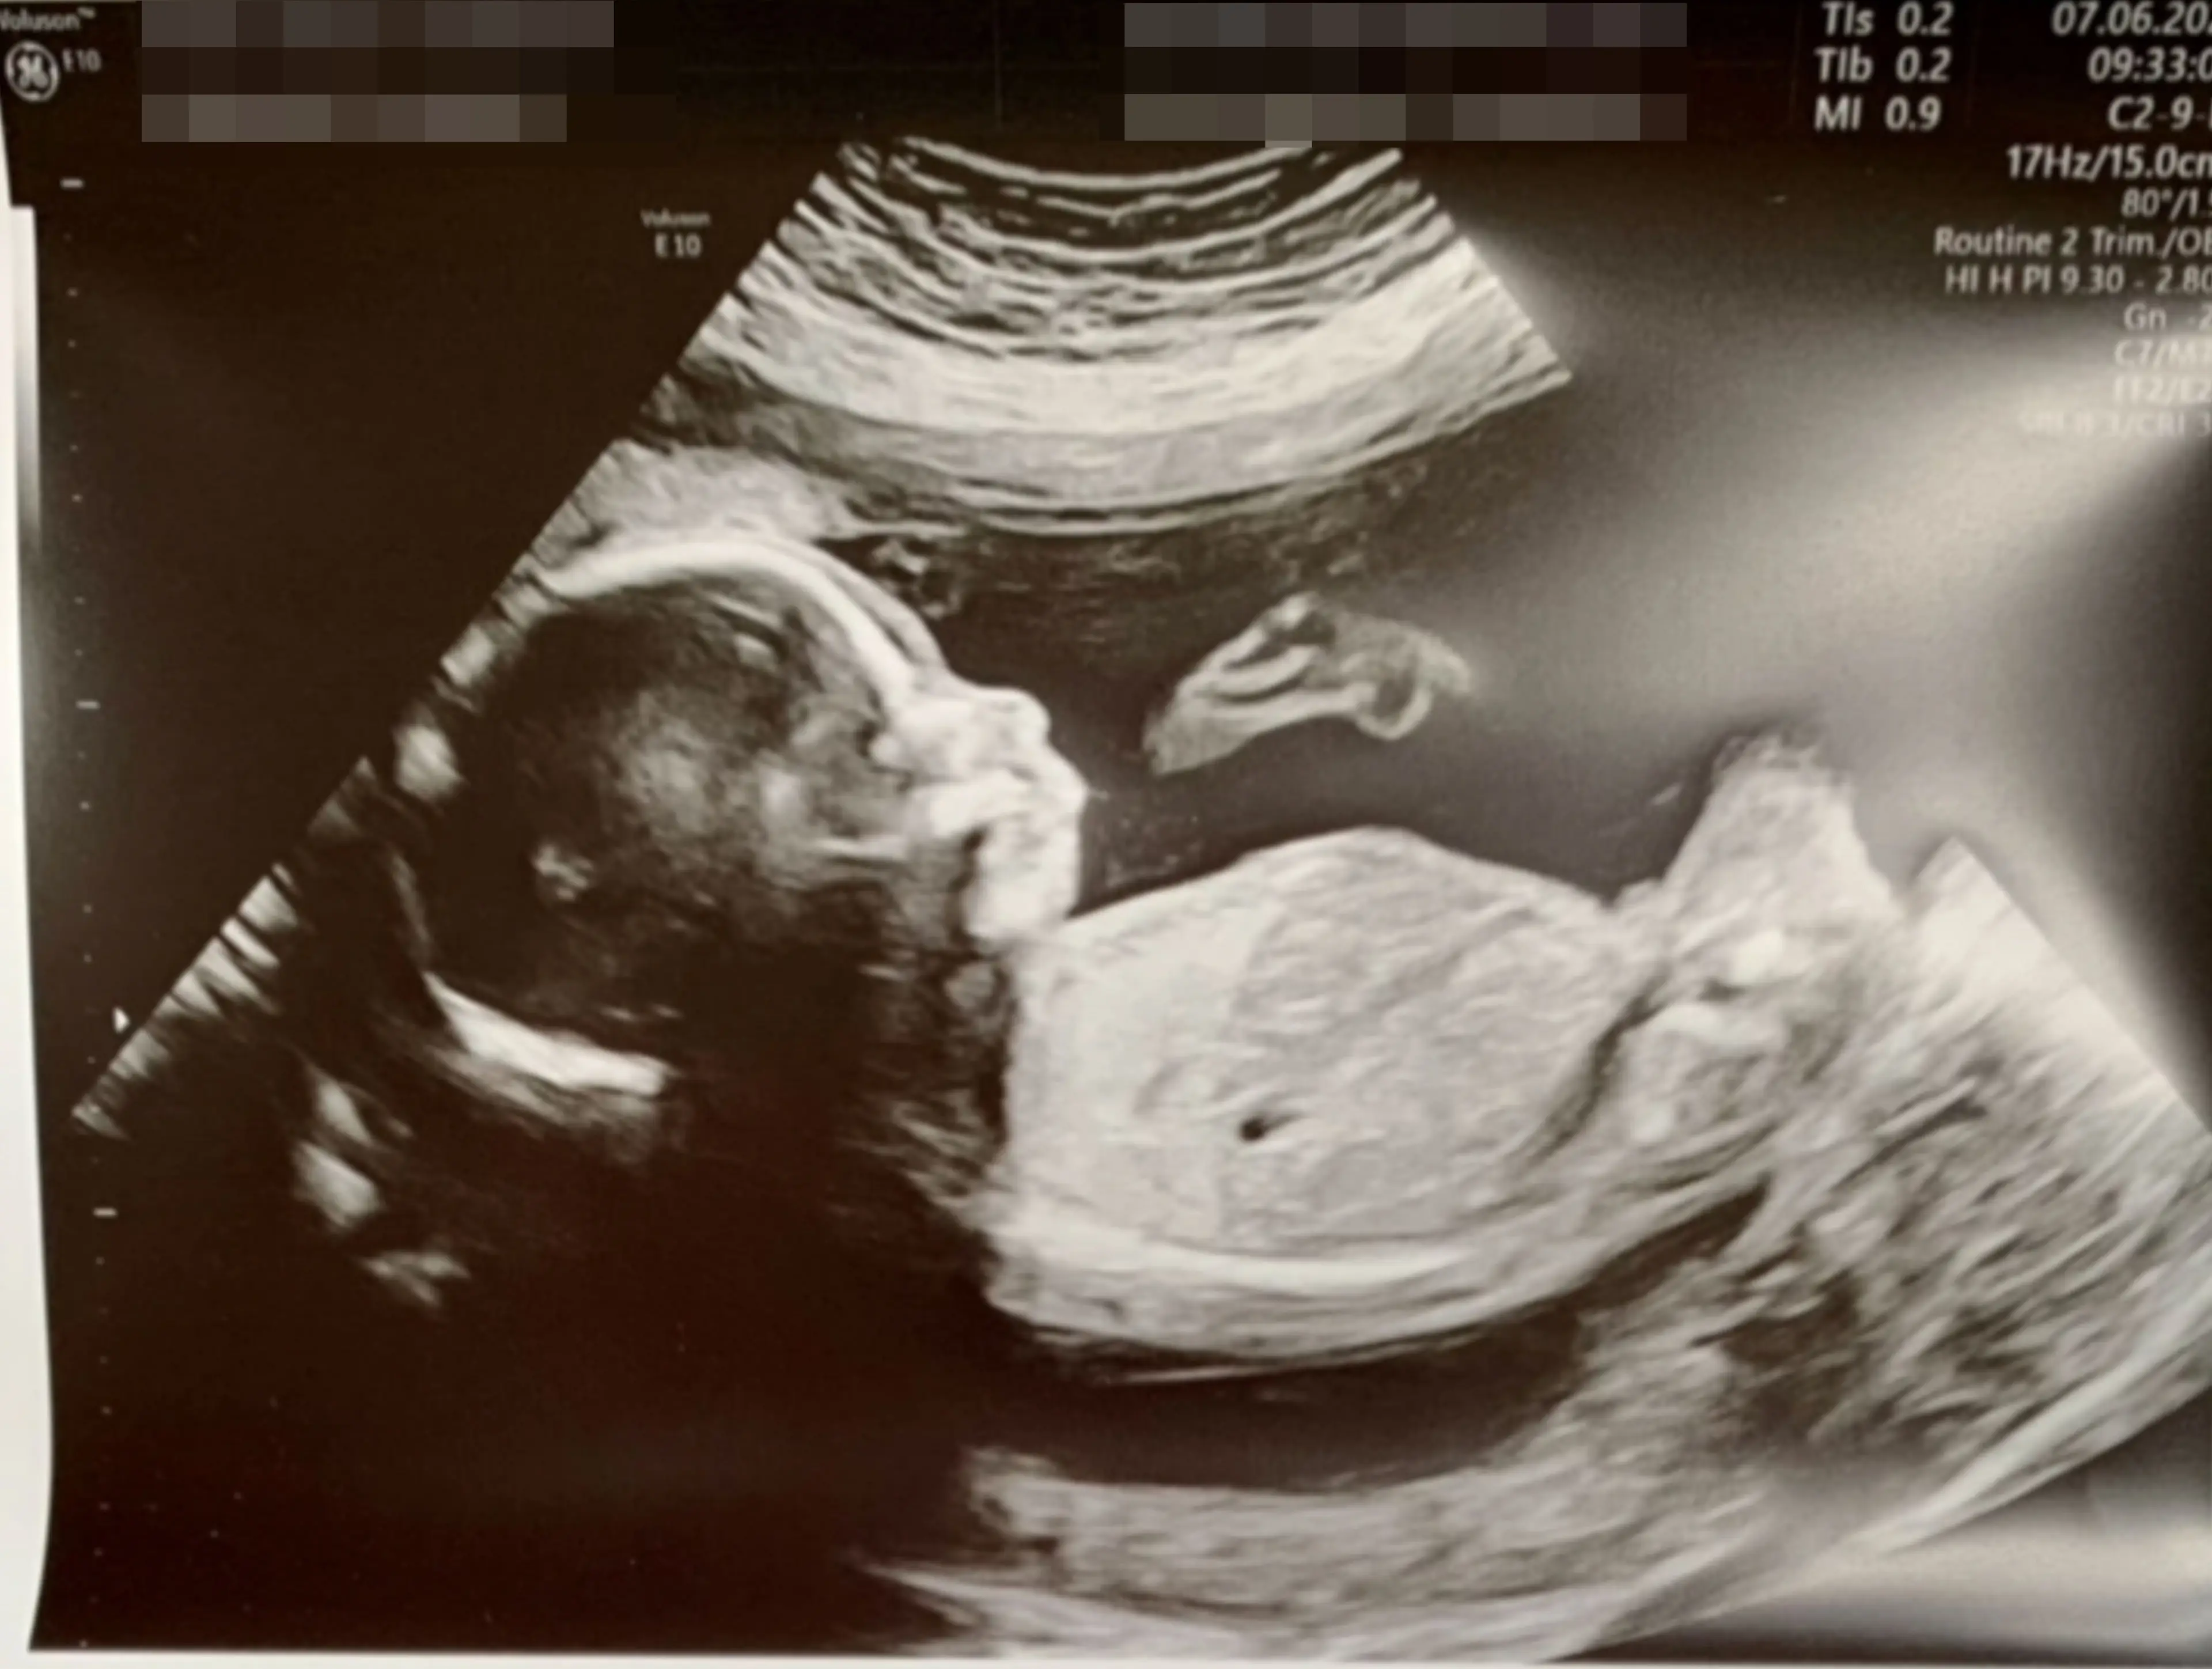

The couple are now expecting a baby boy due in October.